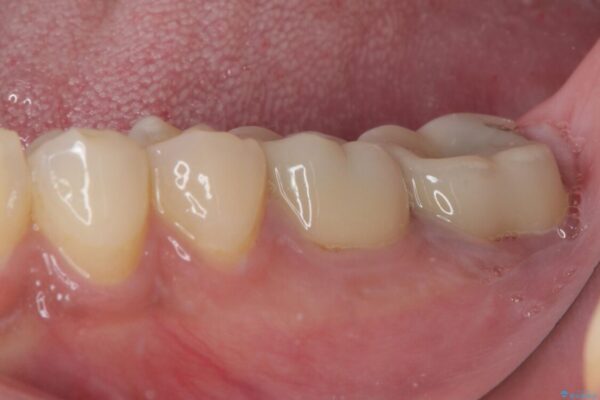

• 海外赴任前に治したい 割れてしまった奥歯のオールセラミッククラウン 治療前画像